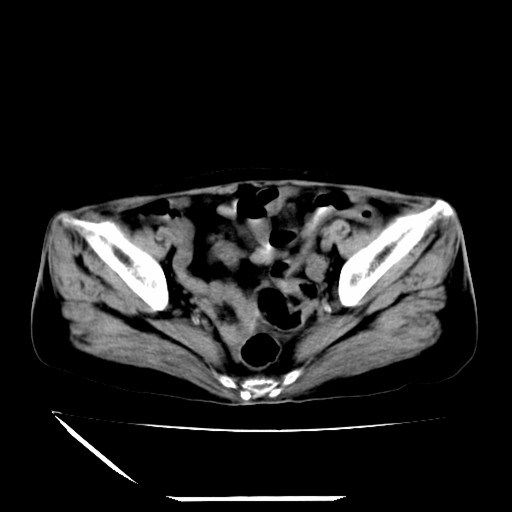

标题: CT16840:女-63岁,下腹部疼痛, [打印本页]

标题: CT16840:女-63岁,下腹部疼痛,

补充资料:血象是13.5,临床拟诊阑尾炎

本人诊断是右肾周围炎,阑尾炎,盆腔少许积液!

诊断右肾周围炎是因为我图像没有发完,诊断阑尾炎是因为相当于阑尾区连续两个层面可以看到增粗的阑尾显影。

支持阑尾炎!局部腹膜增厚,脂肪密度增高。应该手术治疗。